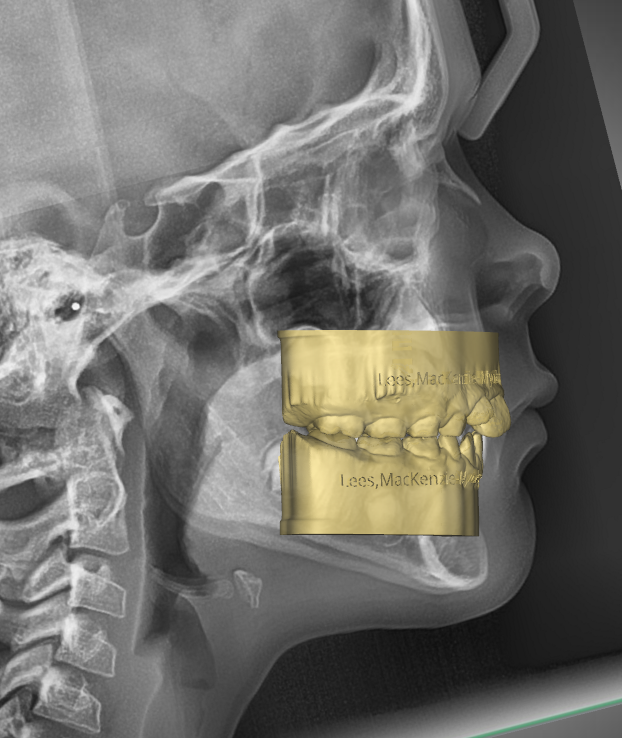

TREATMENT STARTED AT AGE : 9

- Myobrace K1 Medium

- Mixed Dentition

- Class 2 Div I

- Moderate